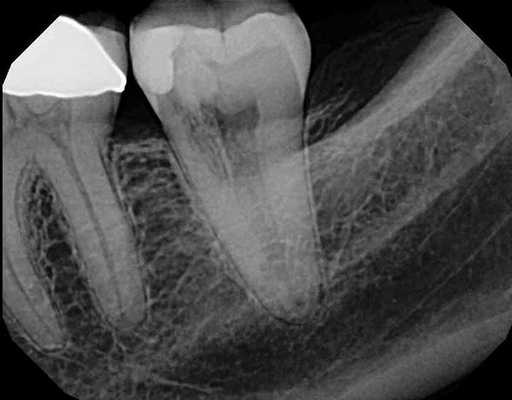

Классически предполагалось, что внутренняя резорбция витальных зубов развивается из-за травматического поражения пульпы (фото 1), а внешняя резорбция случается строго в девитальных зубах (фото 2). К последней могут привести травма периодонтальной связки вследствие воздействия внешних факторов, давления, которое возникает в результате прорезывания зубов, или же патологии развития (фото 3). Иногда внешняя резорбция наблюдается после проведенного ортодонтического лечения, которое провоцирует повышении активности остеокластов в области цемента и дентина верхушки корня. Большинство врачей конечно же полагаются на знания, полученные в ходе предварительного обучения, но некоторые все же интересуются динамикой развития доказательных фактов относительно тех или иных стоматологических патологий.

Фото 1. Рентгенограмма, демонстрирующая пример внутренней резорбции корня.

Фото 2. Рентгенограмма, демонстрирующая пример внешней воспалительной резорбции корня.

Фото 3. Рентгенограмма, демонстрирующая пример резорбции по причине давления.